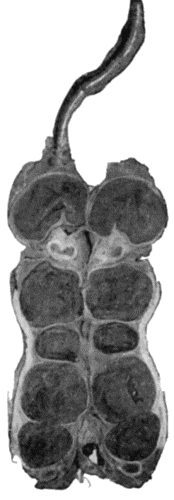

| 111. | Radiogram of Calcification and Ossification in Biceps and Triceps | 418 |

| 112. | Ossification in Muscles of Trunk in generalised Ossifying Myositis | 419 |